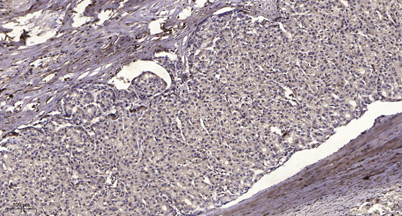

IHC

IHC-p 1:50-300